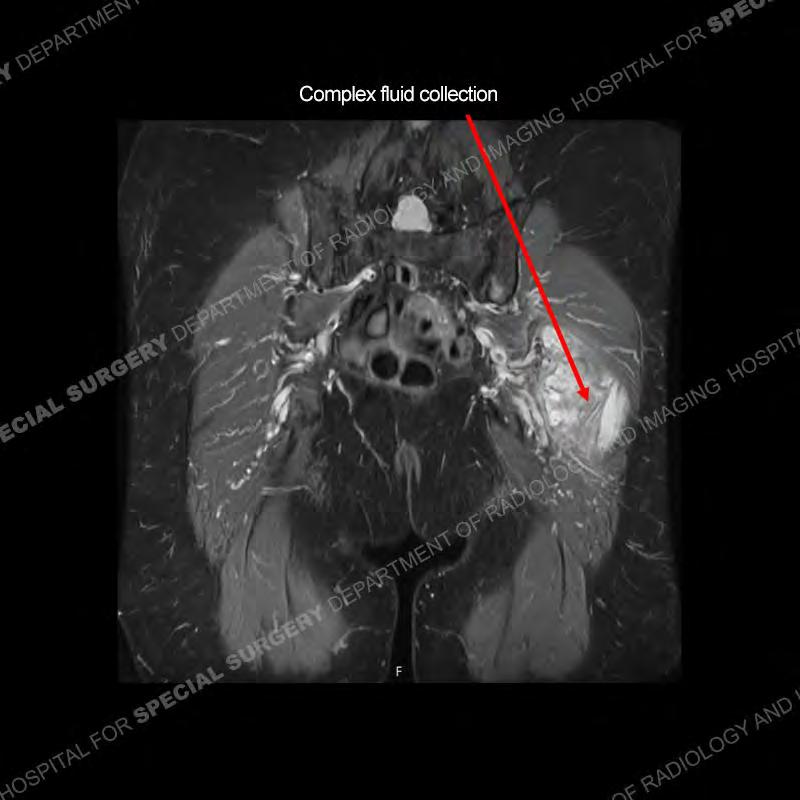

The radiograph is not particularly contributory in this case. The MRI demonstrates markedly abnormal architecture of the gluteus minimus and anterolateral band of the gluteus medius. Portions of the tendons are high signal, portions are highly attenuated, and portions are disrupted. A large, complex fluid collection is present in the adjacent soft tissue.

Diagnosis: Gluteal Tendinosis and Disruption with Complex Trochanteric Bursal Collection

The bursae about the greater trochanter can be a little bit confusing especially given the terminology. Trochanteric bursitis is implied to mean the subgluteus maximus bursa which is present deep to the maximus and just lateral/superficial to the trochanter. That is the bursa involved in this case. In this case the complexity of the bursa relates to the tendon tearing with inflammatory change and probably hemorrhage accounting for the complexity. Two other, less frequently involved bursa are also present. The subgluteus medius and subgluteus minimus bursa are found just deep to the named tendons. Although pathology does frequently follow the previously described pattern it is possible to have isolated pathology to either the medius or minimus.